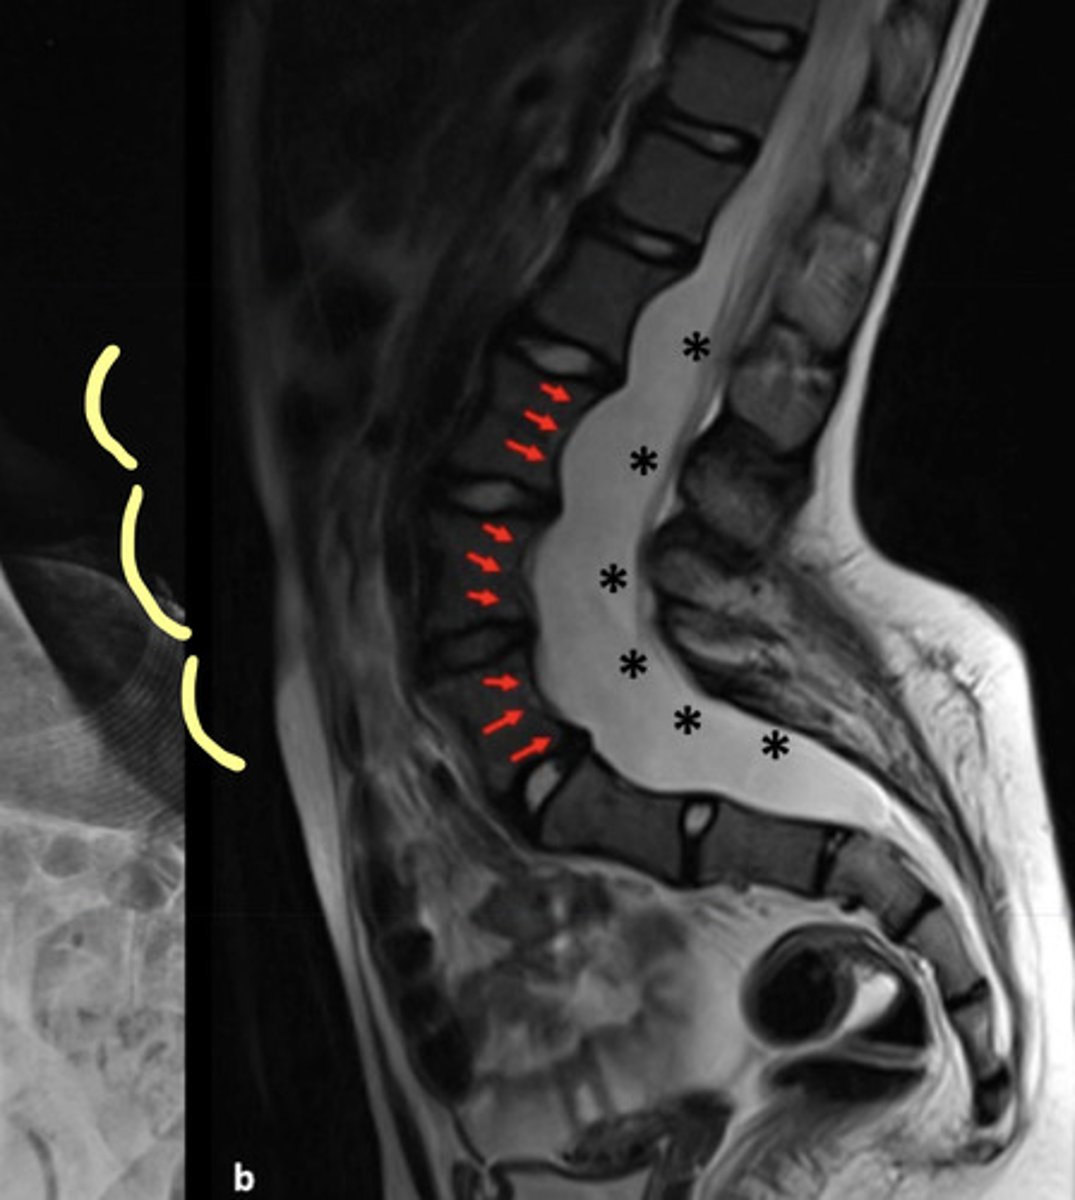

Degenerative Scoliosis

Scoliosis is secondary to degeneration of the ligaments (like the IVD!)

Ribbon-shaped ribs and posterior vertebral body scalloping

Curves must be monitored carefully since they can collapse and rapidly produce paralysis